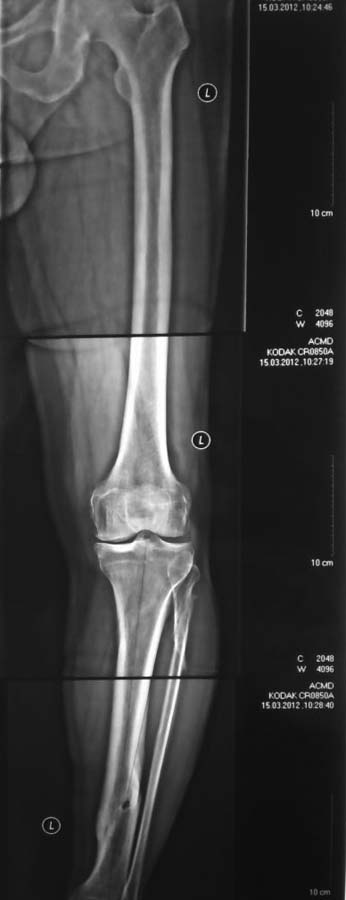

Уважаемый Тарас Рокита,

Обе большеберцовые кости имеют 2 вершины деформации, т.е. речь идет о двухуровневых корригирующих остеотомиях. И только после этого ставить вопрос об одномыщелковом протезировании. При тотальном протезировании, возможно, можно будет обойтись только диафизарными остеомиями

(дистальная CORA). К сожалению, точнее сказать не могу - для расчетов Рг низкого качества.

Я бы сделал рентген в вальгус-стрессе и именно по нему бы чертил оси.